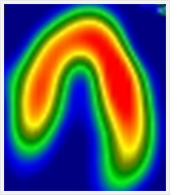

安静時心筋血流シンチグラフィ

心臓の筋肉に酸素や栄養を供給する冠動脈が狭窄または閉塞すると、心臓は虚血状態になり、心筋梗塞に陥ります。心筋細胞の状態(虚血部位、梗塞範囲)を調べる目的で行われる検査です。

1.前準備として食事・水分の制限は特に必要ありません。

2.心筋血流シンチグラフィ用の検査薬を静脈注射します。

3.検査薬が心臓の筋肉に集まるのに約30分かかるため、注射後30分経てから撮影を開始します。

4.検査薬は肝・胆道系から排泄されるため、妨げにならないように検査開始直前に必ず水分を少し摂取していただきます。

5.撮影時間は約30分かかります。

6.健康な心臓の筋肉には通常良く集まり、障害がある場合はその障害の程度に応じた集積の低下がみられます。